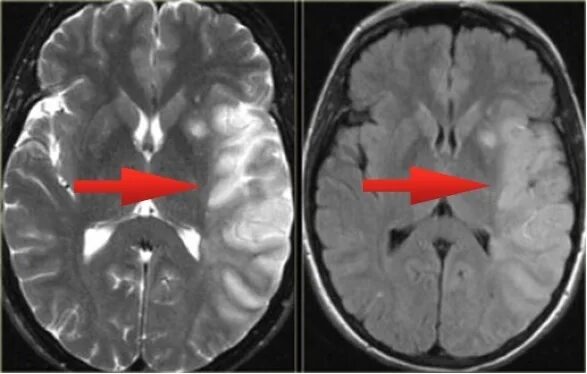

После мрт головного мозга